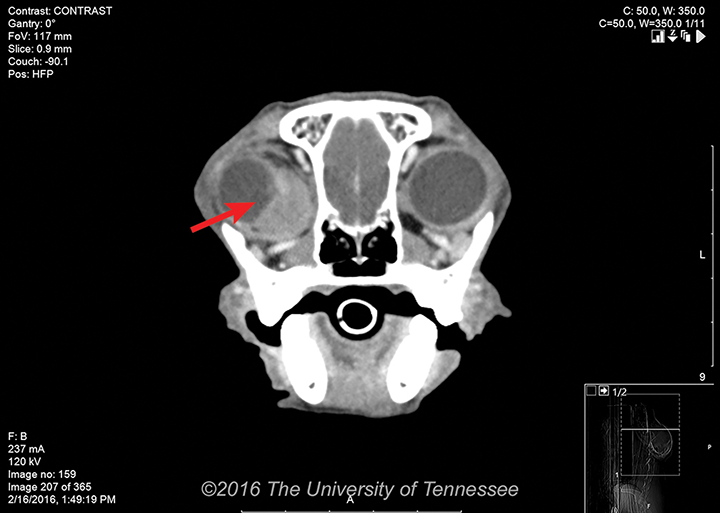

Common orbital neoplasms include carcinomas (eg, squamous cell carcinoma, adenocarcinoma), sarcomas (eg, osteosarcoma, fibrosarcoma), meningioma, and lymphoma.2   Tumors may extend from local tissues (eg, sinonasal cavities) or originate from the bony or soft tissue structures of the orbit; metastasis from distant sites occurs less often. Orbital mass diagnosis can be confirmed using a combination of imaging (eg, ultrasonography, CT, MRI) and biopsy sampling of associated tissues (Figure 2). Bony lysis is a common finding with many neoplasms.